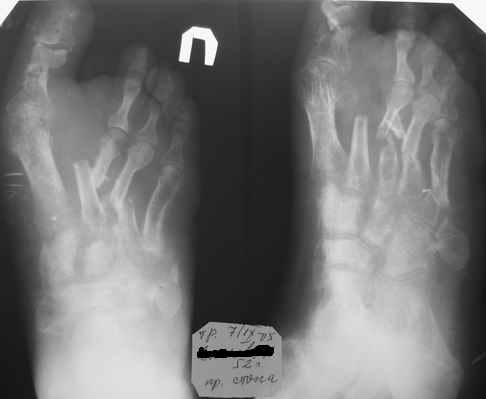

Здравствуйте, Тимур Вячеславович. Спасибо за живой интерес к проблеме: этапы к Вам понял. Насчет ампутации, я думаю, что больной еще не созрел, наоборот- полон оптимизма. Вот свежие рентгенограммы и стопа на 5 день после операции. Появились грануляции, но рана глубокая- 2-2,5 см. Хотелось бы узнать о Вашей тактике на ближайший период, если это возможно. С уважением, Алексей

Здравствуйте, Алексей. А на самом деле все не так уж и плохо. По моему сейчас нужно купировать воспалительный процесс, добиться заживления раны а затем думать о реконструктивной операции. а пока, после появления обильных грануляций ванночки со слабым раствором марганцовки (3-4 кристаллика) до полной готовности кожных покровов (каждый день по 2-3 раза).